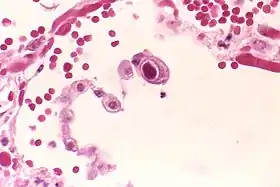

![]() Inclusão intranuclear típica de "olho de coruja" indicando infecção por CMV de um pneumócito pulmonar.[2] | |||||